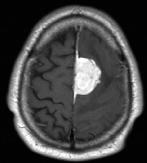

Tumoren

Behandlung von Kalottentumoren mit Kalottendefektdeckung